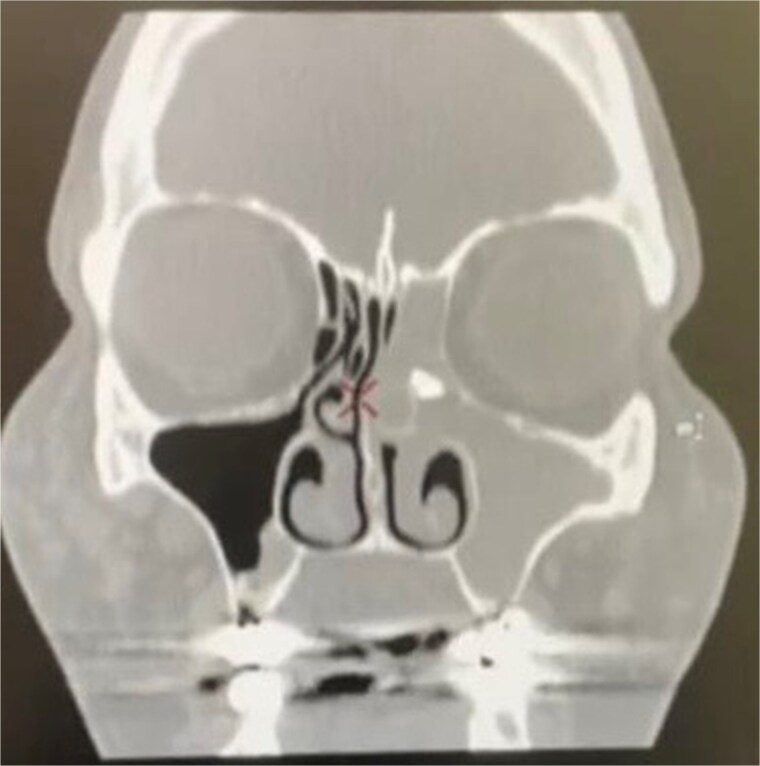

医源性牙源性异物是罕见的,经常累及上颌窦。我们报告一个不寻常的病例牙根迁移到筛窦后拔牙。54岁女性,6个月前拔除上颌左磨牙,出现左侧鼻塞、绿色恶臭鼻分泌物、低鼻血、左侧面部压力3个月的症状。她被诊断为单侧鼻窦炎,鼻内窥镜显示严重的左中道水肿并浓脓排出。鼻窦计算机断层扫描显示左侧前筛窦有一不透射线的异物,左侧鼻窦完全浑浊。通过功能性内窥镜鼻窦手术经鼻拔出牙根。术后症状完全缓解。鼻腔异物刺激粘膜可引起鼻窦炎。由于手术时间短,围手术期发病率低,内镜下拔牙是一种最佳的治疗方法。

Iatrogenic foreign bodies of dental origin are rare and frequently involve the maxillary sinuses. We report an unusual case of tooth-root migration into the ethmoid sinus after dental extraction. A 54-year-old woman with a history of maxillary left molar extraction 6 months prior presented with symptoms of left nasal obstruction, green malodorous nasal discharge, hyposmia, and left-sided facial pressure for 3 months. She was diagnosed with unilateral sinusitis, and nasal endoscopy revealed severe left middle meatus edema with thick pus discharge. Computed tomography of the paranasal sinuses revealed a radiopaque foreign body in the left anterior ethmoid sinus with complete opacification of the left paranasal sinuses. The tooth root was extracted transnasally via functional endoscopic sinus surgery. Complete symptom resolution was achieved postoperatively. Sinonasal foreign bodies can cause sinusitis owing to mucosal irritation. Endoscopic extraction is an optimal treatment owing to its short operative time and reduced perioperative morbidity.